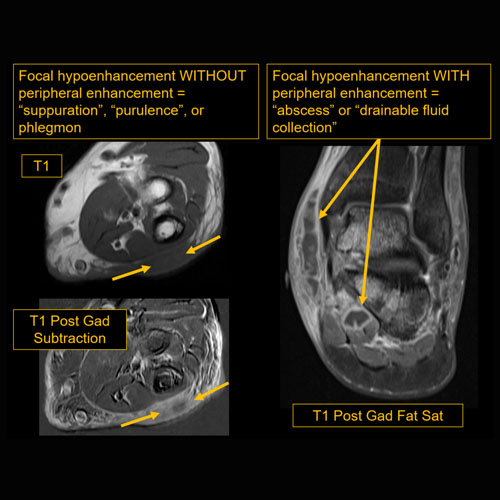

There is confluent hypoenhancement to suggest phlegmon, suppuration, abscess, or drainable fluid collection in the hypodermis. [Yes/No]

There is hypoenhancement, lack of enhancement, or organized fluid collection. [Yes/No]